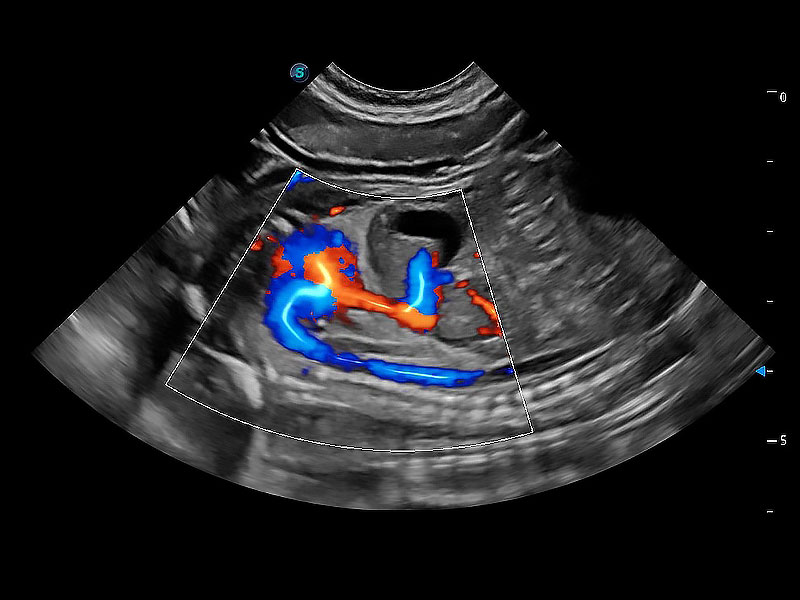

极大提升超低速微细血流的检出能力,同时更精准地滤除软组织和超声信号,为兽用医生提供以往无法通过常规血流获得的疾病诊断信息。

在传统二维血流成像的基础上,呈现血流的立体感,具有动感的生命力之美。即便是微小的血管也能轻松应对,提高了血流的视觉敏感性。